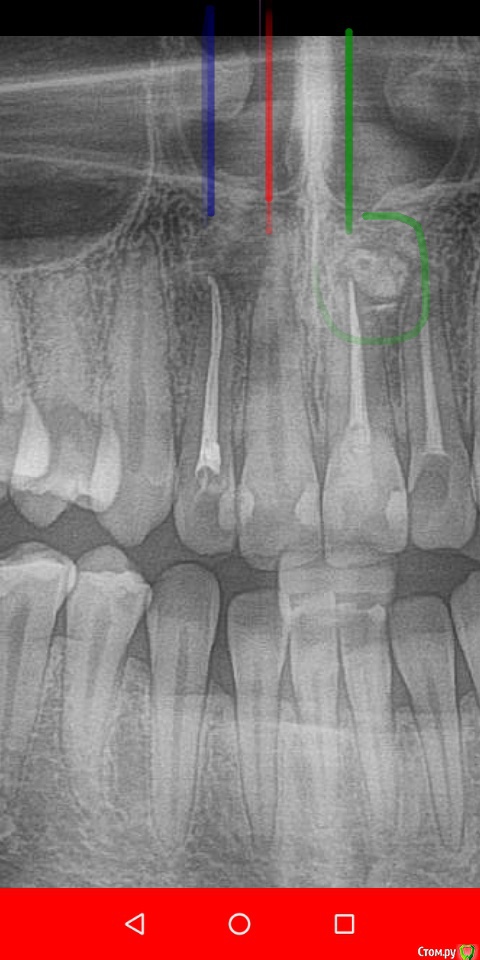

Daria_357 Опубликовано 21 августа, 2020 Поделиться Опубликовано 21 августа, 2020 Здравствуйте, резко появилась сильная неутихающая боль в 12м зубе, на третий день мне смогли оказать скорую помощь, поставив лекарство(убивающее нерв). Утром боль прошла, но опухло сильно лицо - вскрыли десну, поставив дренаж. Позже канал долго чистили и оставили временную пломбу на две недели. 18.08 приняли решение ставить постоянную пломбу. Первая пломбировка была неудачная-на снимке пломба не доходила до верхушки примерно на миллиметр. Вторая попытка закончилась так же, врач сомневалась, советовалась с коллегой, но оставила как было. На прицельном снимке видно, что не доходит в области "поворота" канала около 1мм, но у меня есть только ортопантомограмма, на ней видно только небольшую темную точку, и есть вид формы канала до пломбировки(прикрепила). По мнению врача, дойти дальше не получается так как канал изогнут. На мой вопрос почему тогда с временной пломбой пломбировка была идеальной(там пломба шла выше чем сейчас и истончалась к кончику), - врач сказала, что тогда канал был более узким, а сейчас она его расширила(?). Так же врач высказывала мнение, что если канал не запломб.до конца, то ничего страшного, - сделаем резекцию. Скажите, пожалуйста, стоит ли мне наставивать на перепломбировке уже сейчас, а не дожидаясь воспаления?Этот зуб отмечен синим. И второй вопрос по поводу плана лечения. Мне хотят с соседним передним зубом то же самое делать уже сейчас, так как есть опасения, что воспаление приблизится к нему. Верно ли это? Этот зуб отмечен красным. В этой же клинике мне года три назад вывели промбировочный материл за канал, достаточно много, но вариант, что воспаление из-за этого не подтвердили.Этот зуб отмечен зелёным. 2 Ссылка на комментарий